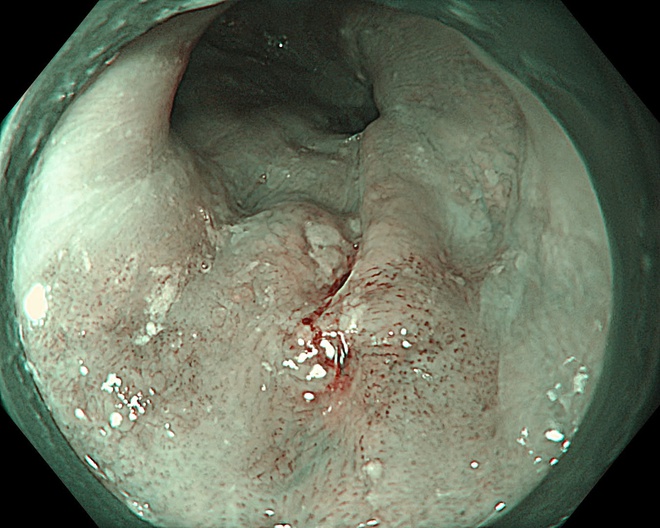

Một bệnh nhân 63 tuổi đã được phát hiện ung thư thực quản giai đoạn sớm nhờ công nghệ này và điều trị thành công, xuất viện sau 2 ngày.

Trong một trường hợp khác, bệnh nhân 67 tuổi được phát hiện tổn thương qua nội soi công nghệ cao. Tuy nhiên, qua đánh giá chuyên sâu, bác sĩ xác định tổn thương đã vượt chỉ định điều trị nội soi và chuyển sang phẫu thuật.

Kết quả mô bệnh học sau đó xác nhận ung thư đã xâm lấn dưới niêm mạc, phù hợp với chỉ định ngoại khoa.

Hình ảnh tổn thương thực quản của bệnh nhân.

Thực tế này cho thấy vai trò quan trọng của nội soi công nghệ cao kết hợp với kinh nghiệm lâm sàng trong việc đánh giá chính xác giai đoạn bệnh, từ đó đưa ra phương pháp điều trị phù hợp, tối ưu.